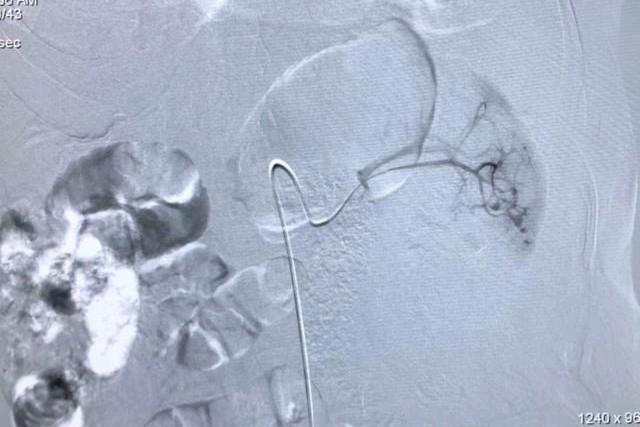

术中造影发现左肾正常形态消失,发现多处血管破裂并伴有造影剂迅速外溢,还在出血,病情非常凶险。夏风飞医生与张主任配合默契,立即应用微导管逐一的对靶向分支血管进行选择造影,查找可能的出血点。采用不同角度,对肾动脉各个分支分别重复造影,术*共中**发现了4条出血血管,在尽量保护仅存的左肾良好组织的前提下,应用微弹圈进行了精确栓塞微创止血治疗。